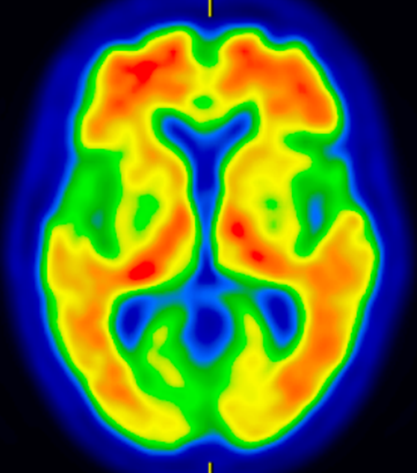

* アミロイドPET(図2):当院で実施可能です。アルツハイマー病の原因物質と考えられているアミロイドβプラークが、脳内に溜まっているかどうかを調べる検査です。抗アミロイドβ抗体薬を使用するには、アミロイドPETが陽性である必要があります。

図2 アルツハイマー型認知症のアミロイドPET